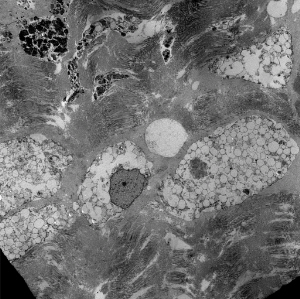

Lysosomal vacuoles and zebra bodies in mucopolysaccharidosis (mitral valve)

Lysosomal vacuoles in mucolipidosis (skin biopsy)